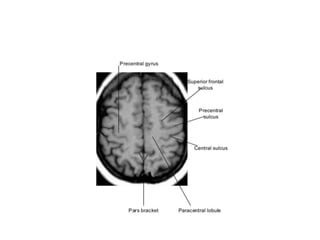

Central Sulcus

Brain lobes

Fig 2a: T1 MRI axial projection. 1: inter-

hemispheric scissure; 2: lateral sulcus; 3:

frontal lobe; 4: insula lobe; 5: temporal lobe; 6:

occipital lobe.

Anatomical Land marks.

• Cortex and division into various lobes.

Fig 2a: T1MRI axial projection. 1: inter- hemispheric scissure; 2: lateral sulcus; 3: frontal lobe; 4: insula lobe; 5: temporal lobe; 6: occipital lobe.